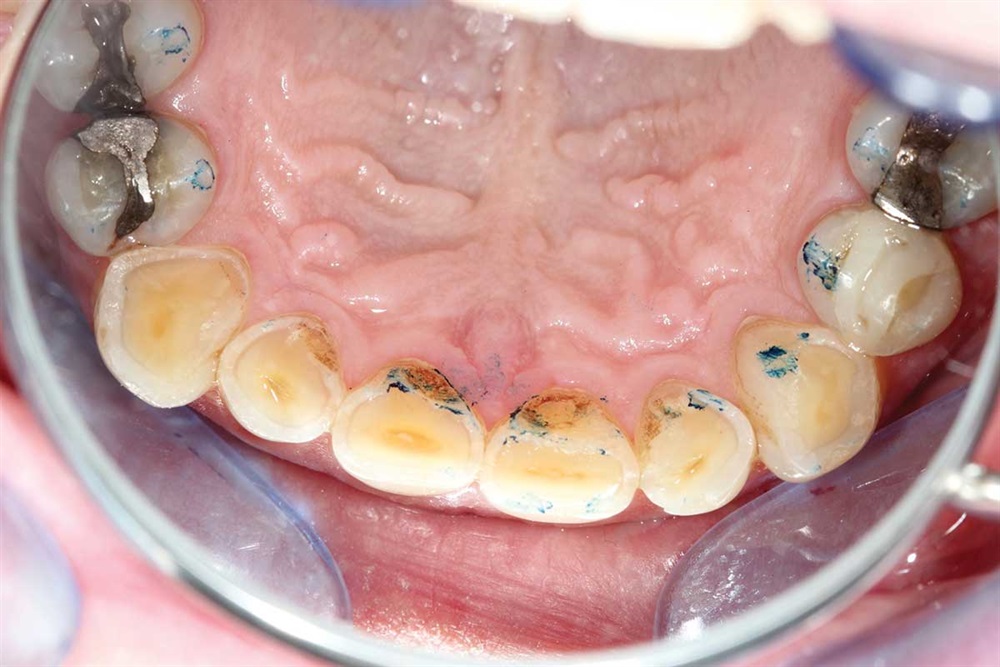

Fig. 1: June 2018. Where did all the tooth structure go? Grinding in protrusion? There is serious wear and tear. This 63-year-old gentleman has been wearing out his teeth, especially in the past 10 years.

Fig. 3: Lower incisors. The patient’s dentists in Ontario wanted to do ortho for 18–24 months and then restorative crowns with many elective root canals, to the tune of a nice luxury car.